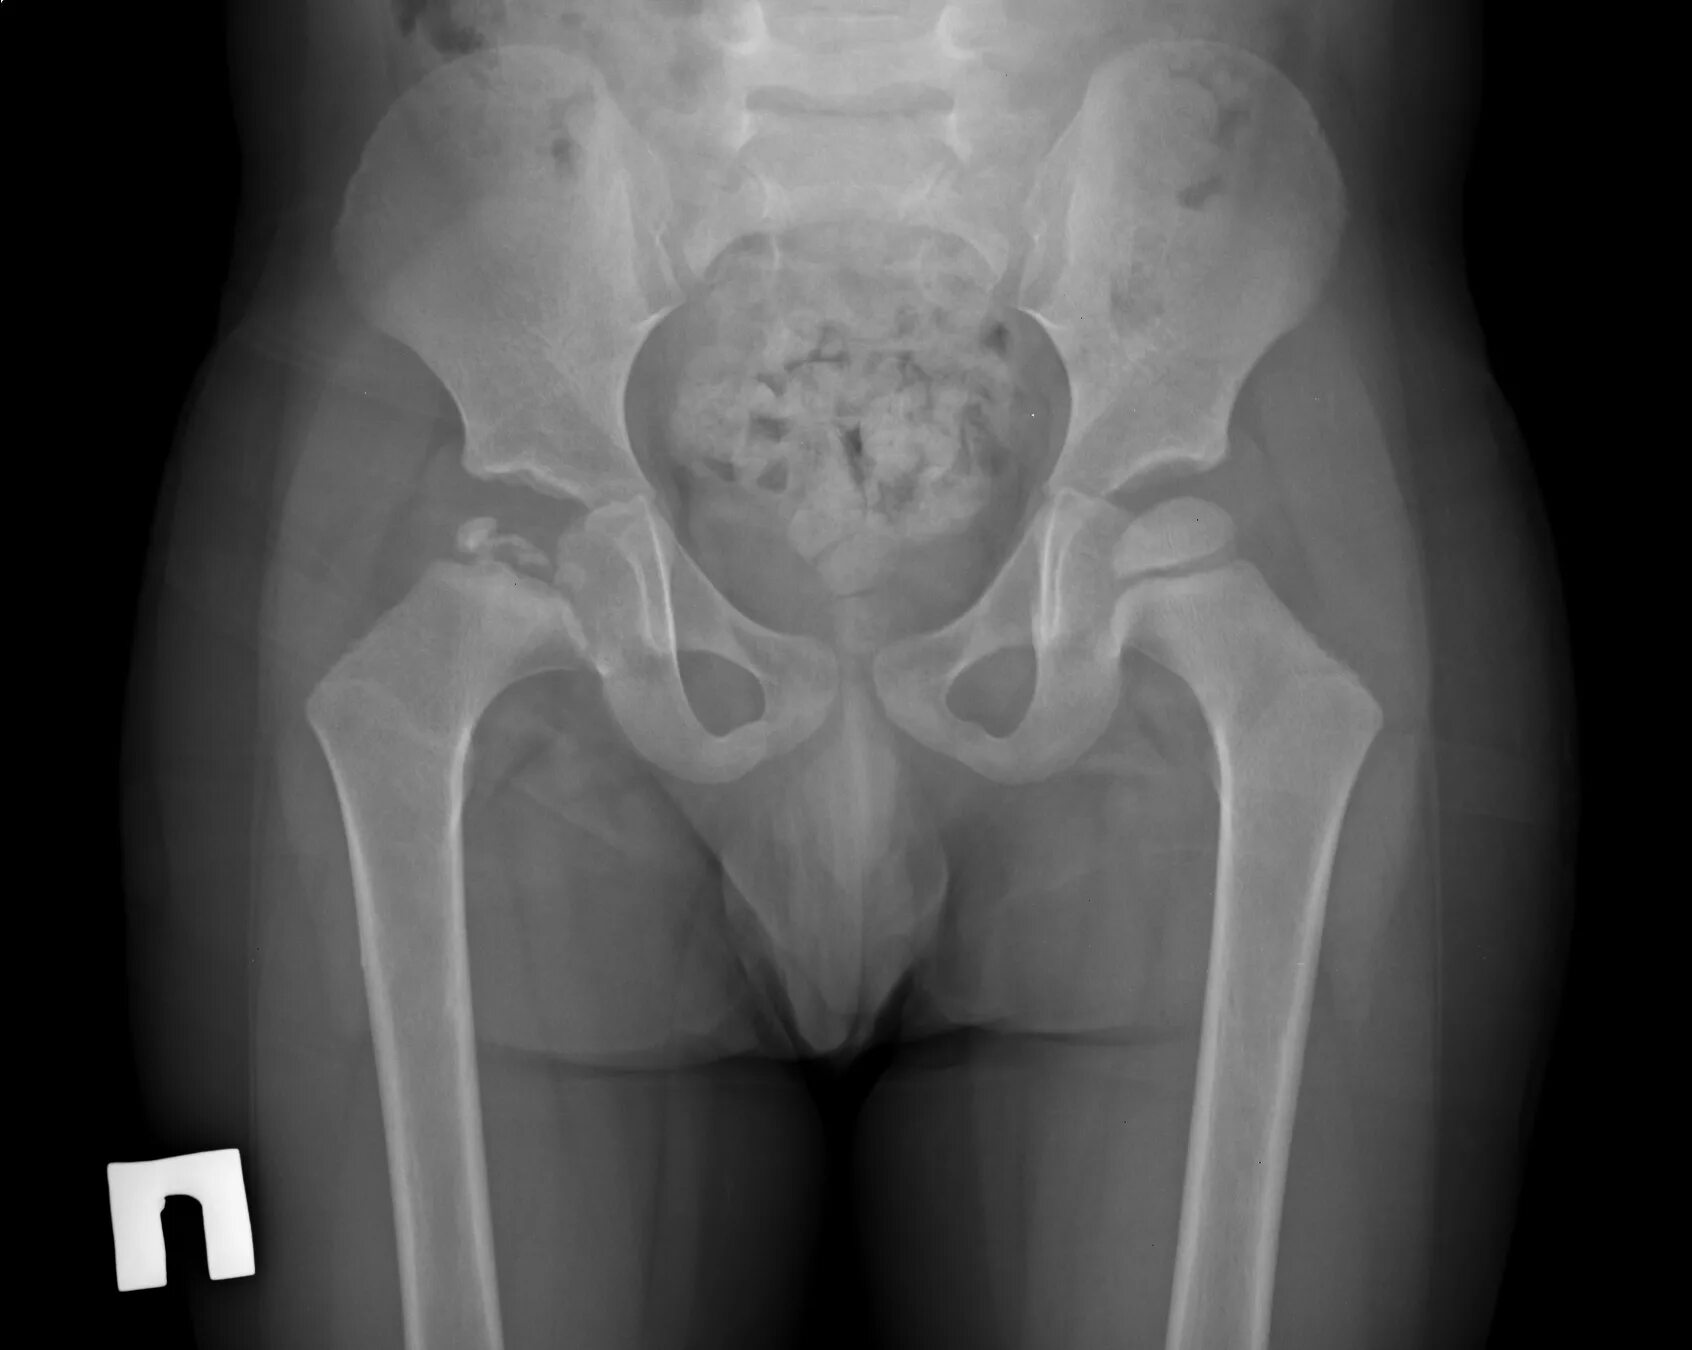

Метастазы в тазобедренном